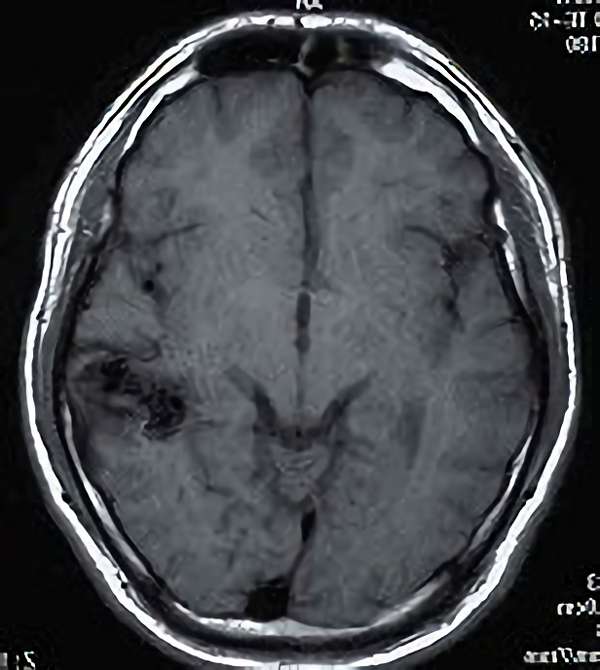

No.450 手術前

No.450 手術中

No.450 手術後

全治。

脳血管撮影により完全除去が確認された